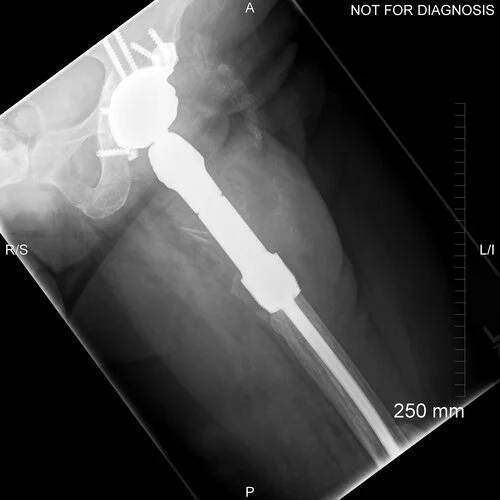

Anteroposterior and lateral plain radiographs demonstrate the new proximal femoral spacer in situ.

Coronal CT scan taken to plan for the custom acetabular component

Two days after the operation this construct dislocated – probably because of the lack of proximal thigh muscles. June was walking at home with a Zimmer frame when she felt a pop in her left hip. She wasn’t in any severe pain but she was uncomfortable.